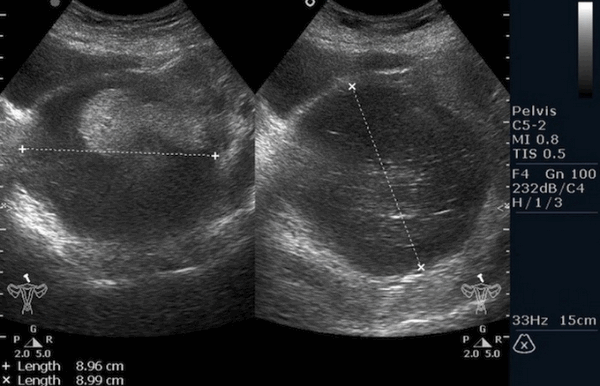

Рисунок 3. - тератома яичника а -УЗИ, б — МРТ.

Ультразвуковое исследование (УЗИ) мошонки является предпочтительным начальным визуализирующим исследованием для оценки образования яичка. УЗИ может подтвердить наличие новообразования, определить его расположение и оценить состояние противоположного яичка (рис. 4). Чувствительность метода достаточно высокая - от 92 % до 98 %.

Компьютерная томография органов грудной клетки, брюшной полости, малого таза используются для оценки распространения опухолевого процесса (рис.5).